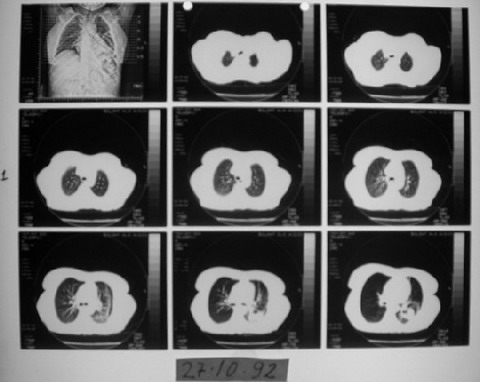

VAKA RAPORU- Teşhis: Maliyn lenfoma, akciğer kanseri - MG

EK MG3

27 Ekim 1992'de çekilen bilgisayarlı tomografi ve değerlendirme raporu.